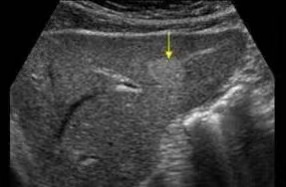

体检超声报告中此“瘤”非彼瘤(图1)

看到“瘤”字,千万不要惶恐,这是一种良性疾病,其发生自发破裂,比中500万大奖的几率还要低。因此,只有当肝血管瘤超过10公分以上,压迫到周围组织器官,才考虑手术治疗。